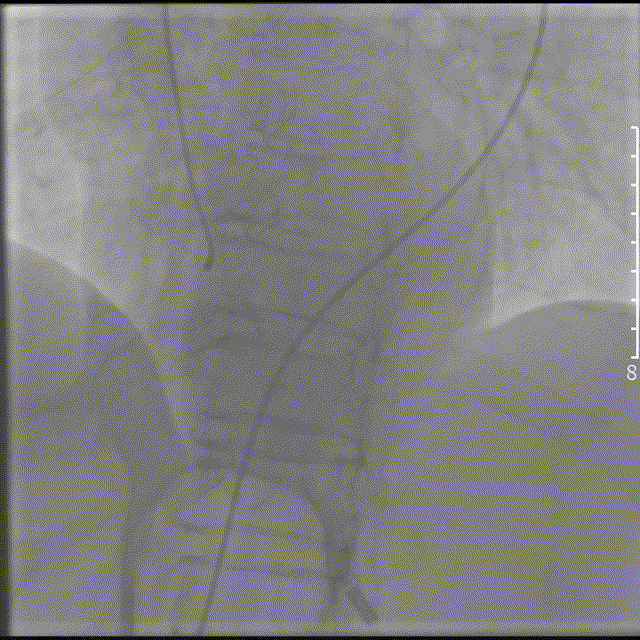

右图:RCA:中段完全闭塞,远端血流TIMI0级。